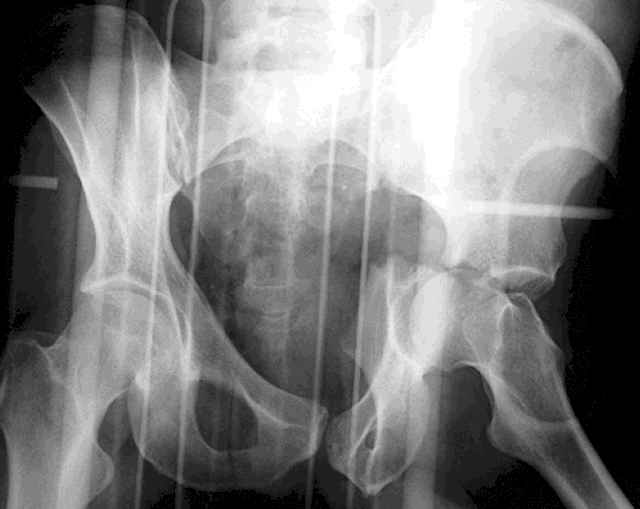

You can adjust the quadrilateral surface contact point as needed to get the fracture to reduce...we plan this based on the fracture orientation on the preop CT scan images...the clamp should be balanced to avoid over compressing one portion and distracting the other limb. Go back to and you¹ll see on the injury CT where the clamp tines need to be.